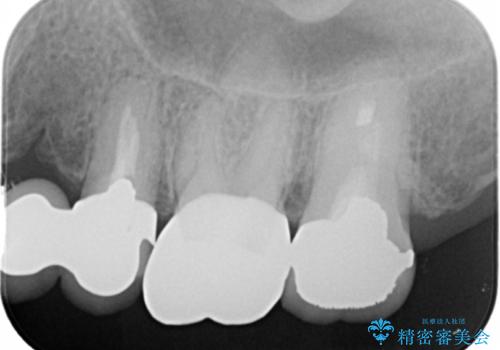

- 左上6 仮歯+フルジルコニアクラウン 11000円+77000円費用は治療当時の料金となります

向かい合わせの歯の咬みこみが強くインレーよりも強度の高いクラウンでの治療となりました。その中でも色が白くある程度の薄さでも耐久性を発揮するフルジルコニアクラウンでの修復を行いました。適合も良く色調もとてもなじんだため大変喜んでいただけました。